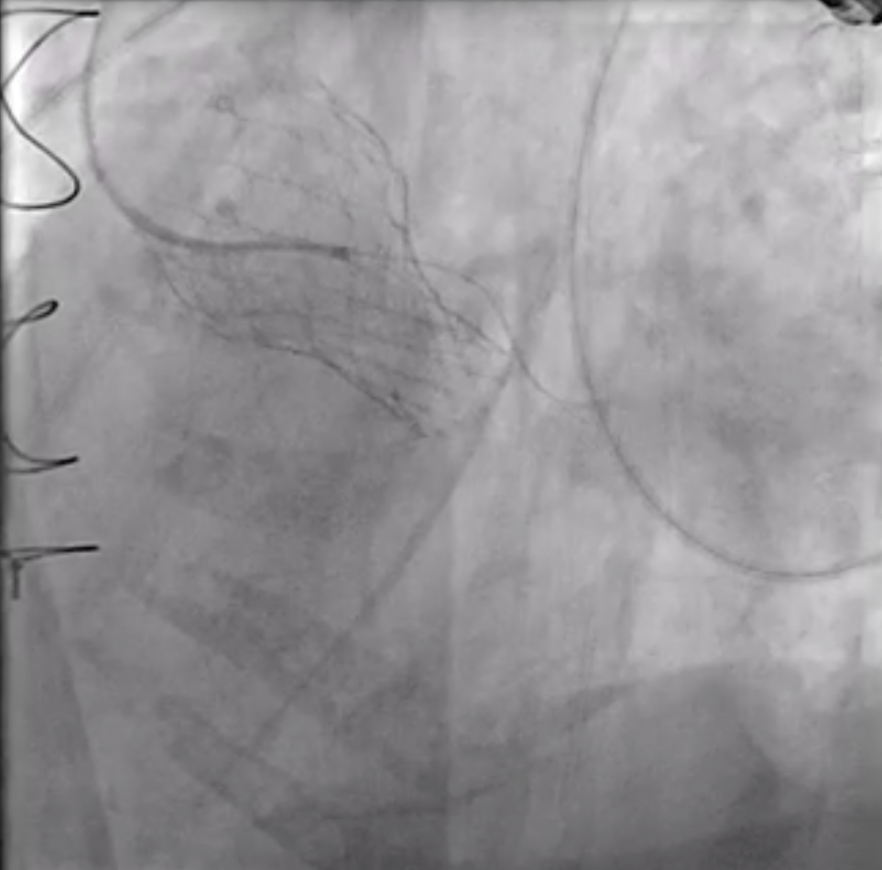

Relevant Catheterization Findings

Aortogram: a paravalvular leakage noted between SAVR and TAVR valveHemodynamic study:- Pulmonary wedge pressure = 18 mmHg- Pulmonary artery pressure = 58/19 mmHg (mean 37 mmHg)- RV pressure = 71/5 mmHg- RA mean pressure = 9 mmHg- IVC pressure = 9 mmHg- Cardiac output (thermodilution): 3.73 L/min- PVR = 5 woods (408 Dynes.sec.cm-5)

Aortogram (5_17 angio).mp4

Under local anesthesia, the RFA was punctured, and a 6-Fr sheath was introduced. A 6-Fr pigtail catheter over a 0.035-inch J-tip wire was advanced into the ascending aorta, and an aortogram demonstrated a moderate PVL originating from the surgical valve ring and the aortomitral curtain.The pigtail catheter was replaced with a 6-Fr MPA2 catheter to delineate the anatomy of the transcatheter heart valves and PVL. A 6-Fr JL 3.5 catheter was then used for a nonselective left coronary angiogram, confirming the PVL adjacent to the aortic annulus. A Terumo guidewire was advanced through an Amplatz Left (AL1) catheter and successfully crossed the PVL into the left ventricle (LV).For device delivery, the LFA was also punctured, and a 6-Fr sheath was inserted. A pigtail catheter was placed in the ascending aorta to identify the left main ostium. Attempts to advance an AGA Amplatzer Vascular Plug (AVP) 10/7 mm through the PVL were made using multiple guiding systems, including AL and JR4 catheters, a 6-Fr Shuttle sheath, and a Superstiff 0.035-inch wire, but initial passage into the LV was unsuccessful.Balloon sizing was performed using a Boston Scientific Mustang balloon (4.0 mm ¡¿ 20 mm ¡¿ 75 cm) inflated to 4 atm. The 6-Fr sheath was exchanged for a 7-Fr sheath, and a 7-Fr Boston MP 90-cm guiding catheter was advanced into the LV. An AGA Amplatzer Vascular Plug 10/7 mm was successfully deployed across the PVL. Final aortography confirmed successful occlusion of the PVL.